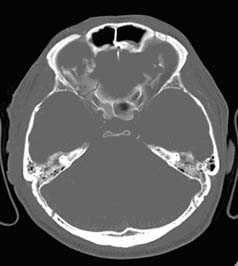

КТ позволяет последовательно изучить мягкие ткани головы, кости черепа, вещество мозга, эпидуральные, субдуральные, субарахноидальные пространства, цистерны основания и желудочки мозга:

- выявить переломы свода и основания черепа (с чувствительностью, намного превышающей традиционную рентгенографию) ,

Визуализация минимальных количеств излившейся свежей крови, уверенная дифференциация ее от других внеклеточных жидкостей, слежение за динамикой отека и набухания головного мозга, некроза и восстановления его структур с одновременным распознаванием переломов костей черепа, особенно его основания, составляют преимущества КТ перед магнитно-резонансной томографией.